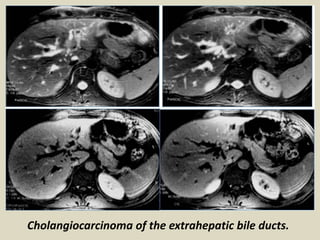

Cholangiocarcinoma of the extrahepatic bile ducts.

Cholangiocarcinoma of theextrahepatic bile ducts.